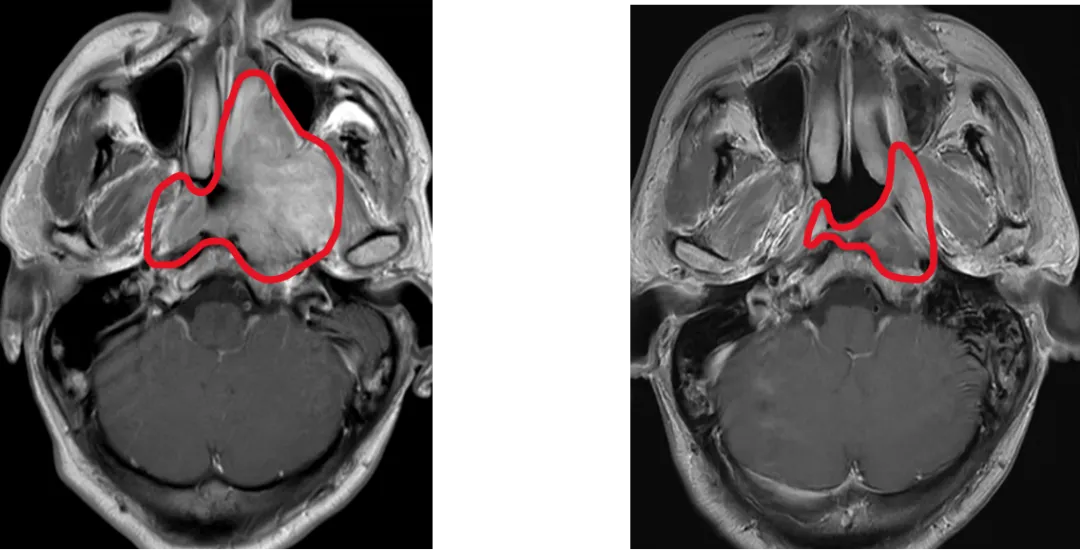

鼻咽癌高發(fā)于中國(guó),新發(fā)病例占全球47%。放射治療是鼻咽癌的根治手段,但中晚期患者需要在放療前接受化療,放療前化療使90%患者腫瘤縮小,而既往國(guó)際指南推薦放療照射范圍仍需包括化療前腫瘤大小覆蓋的范圍,導(dǎo)致周圍正常組織(如內(nèi)耳、腮腺)接受高劑量輻射,引發(fā)聽力損傷、口干等不可逆副作用,嚴(yán)重影響患者生活質(zhì)量。

為此,馬駿院士團(tuán)隊(duì)展開有關(guān)研究,采用了國(guó)際通用的標(biāo)準(zhǔn)多中心、隨機(jī)、平行對(duì)照設(shè)計(jì),納入445例中晚期鼻咽癌患者,隨機(jī)分為兩組:分別基于化療后和化療前腫瘤范圍進(jìn)行放療。主要終點(diǎn)為3年局部區(qū)域無(wú)復(fù)發(fā)生存率,次要終點(diǎn)包括毒副反應(yīng)和生活質(zhì)量。

這項(xiàng)多中心III期臨床試驗(yàn)證實(shí),僅照射化療后的腫瘤范圍,并沒有增加復(fù)發(fā),卻顯著降低了毒副反應(yīng),顯著改善患者生活質(zhì)量,使我國(guó)鼻咽癌診療實(shí)現(xiàn)從“保生存”到“優(yōu)生存”的跨越式突破。3年局部區(qū)域無(wú)復(fù)發(fā)生存率達(dá)91.5%(與傳統(tǒng)療法持平);嚴(yán)重放射性口腔黏膜炎降低4成,晚期嚴(yán)重中耳炎發(fā)生率銳減5成,口干癥狀改善6成;整體健康狀態(tài)、體力狀態(tài)、情緒功能顯著改善,口干及唾液黏稠癥狀減輕。